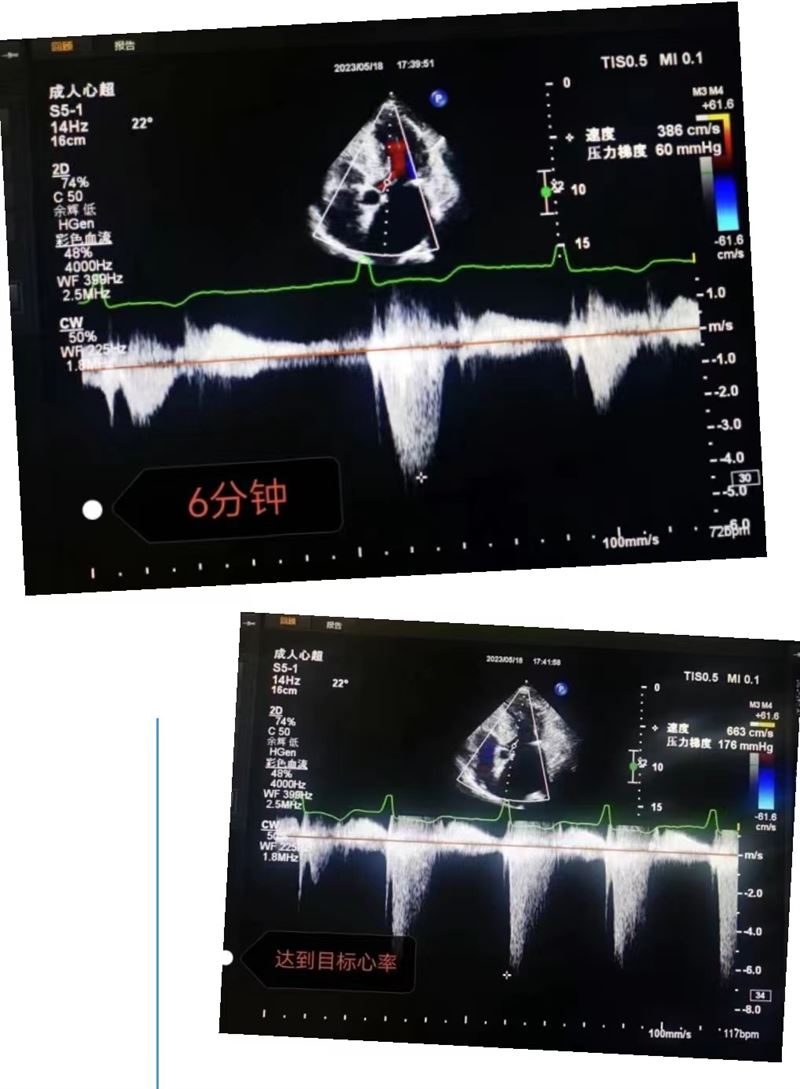

超声科王英莉主任及心血管组贾贝主治医师、陈辉主管护师及牛丹青护师为该患者行药物负荷超声心动图。监护仪、急救车到位,常规经胸超声心动图提示室间隔增厚,左室流出道血流速度略增快,左心腔超声造影,可清晰显示室壁显著增厚,符合肥厚型心肌病表现,随后又进行了多巴酚丁胺负荷超声心动图,静息状态下显示左室流出道血流速度V:207cm/s,PG:17mmHg;3分钟后心率达75次/分,左室流出道血流速度V:218cm/s,PG:19mmHg;6分钟后心率达94次/分,左室流出道血流速度V:386cm/s,PG:60mmHg;9分钟后达到目标心率,左室流出道血流速度V:649cm/s,PG:169mmHg,停止用药,药物负荷试验阳性,检查过程中患者无不适症状,最终诊断为隐匿性肥厚型梗阻性心肌病。